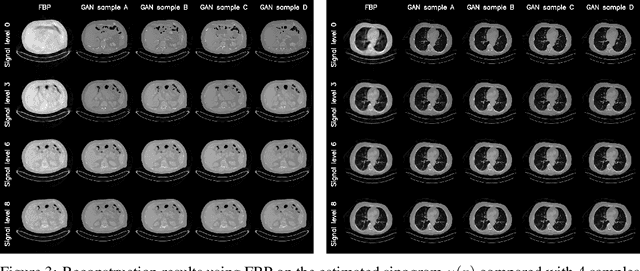

We propose an end-to-end differentiable architecture for tomography reconstruction that directly maps a noisy sinogram into a denoised reconstruction. Compared to existing approaches our end-to-end architecture produces more accurate reconstructions while using less parameters and time. We also propose a generative model that, given a noisy sinogram, can sample realistic reconstructions. This generative model can be used as prior inside an iterative process that, by taking into consideration the physical model, can reduce artifacts and errors in the reconstructions.